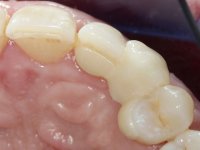

The proposed treatment results from the limitations imposed by the patient, who refused an orthodontical pull of the canine into the edntulous space, and was unwilling to extract the impacted canine and place an implant in the zone of 1.3. Thus, the confection of a Maryland Bridge was proposed, with a Zr infrastructure and two retainers. The mesial retainer would be bonded to the palatal face of the tooth 1.2 and the distal retainer was to be bonded to the palatal wall of tooth 1.4.

To define the dental zone to be covered by the Maryland bridge retainers, the patient was asked to perform maximum intercuspidation movements, and the contact points were marked with articular paper. Tooth preparation of the interproximal surfaces was made, to create a prosthetic insertion axis. It was sought that the mesio-distal diameter at the incisal level was equal to the diameter mesio-distal at the cervical level, that is to say, the interproximal walls were parallelized. Tooth preparation was done with fine grain diamond drills, and later polishing was done with abrasive discs. Color information was collected even before confection of the impression, to avoid dehydration of the arcade. Definitive impression was made using wash technique impression with silicone of heavy and regular consistency, both with fast setting, and a working plaster model was prepared in the lab. A laboratory scanner was used to scan the working model, and later, the infrastructure for the Maryland bridge was made using a CAD-CAM process. Ceramic was placed on this subframe. A ceramic adhesive was applied to the internal surface of the wings and connectors, which would enable bonding to the adjacent teeth. The adhesive bridge was bonded in the mouth following the conventional bonding technique. After bonding, the protrusion and laterality movements were carefully checked to avoid undesirable contacts.